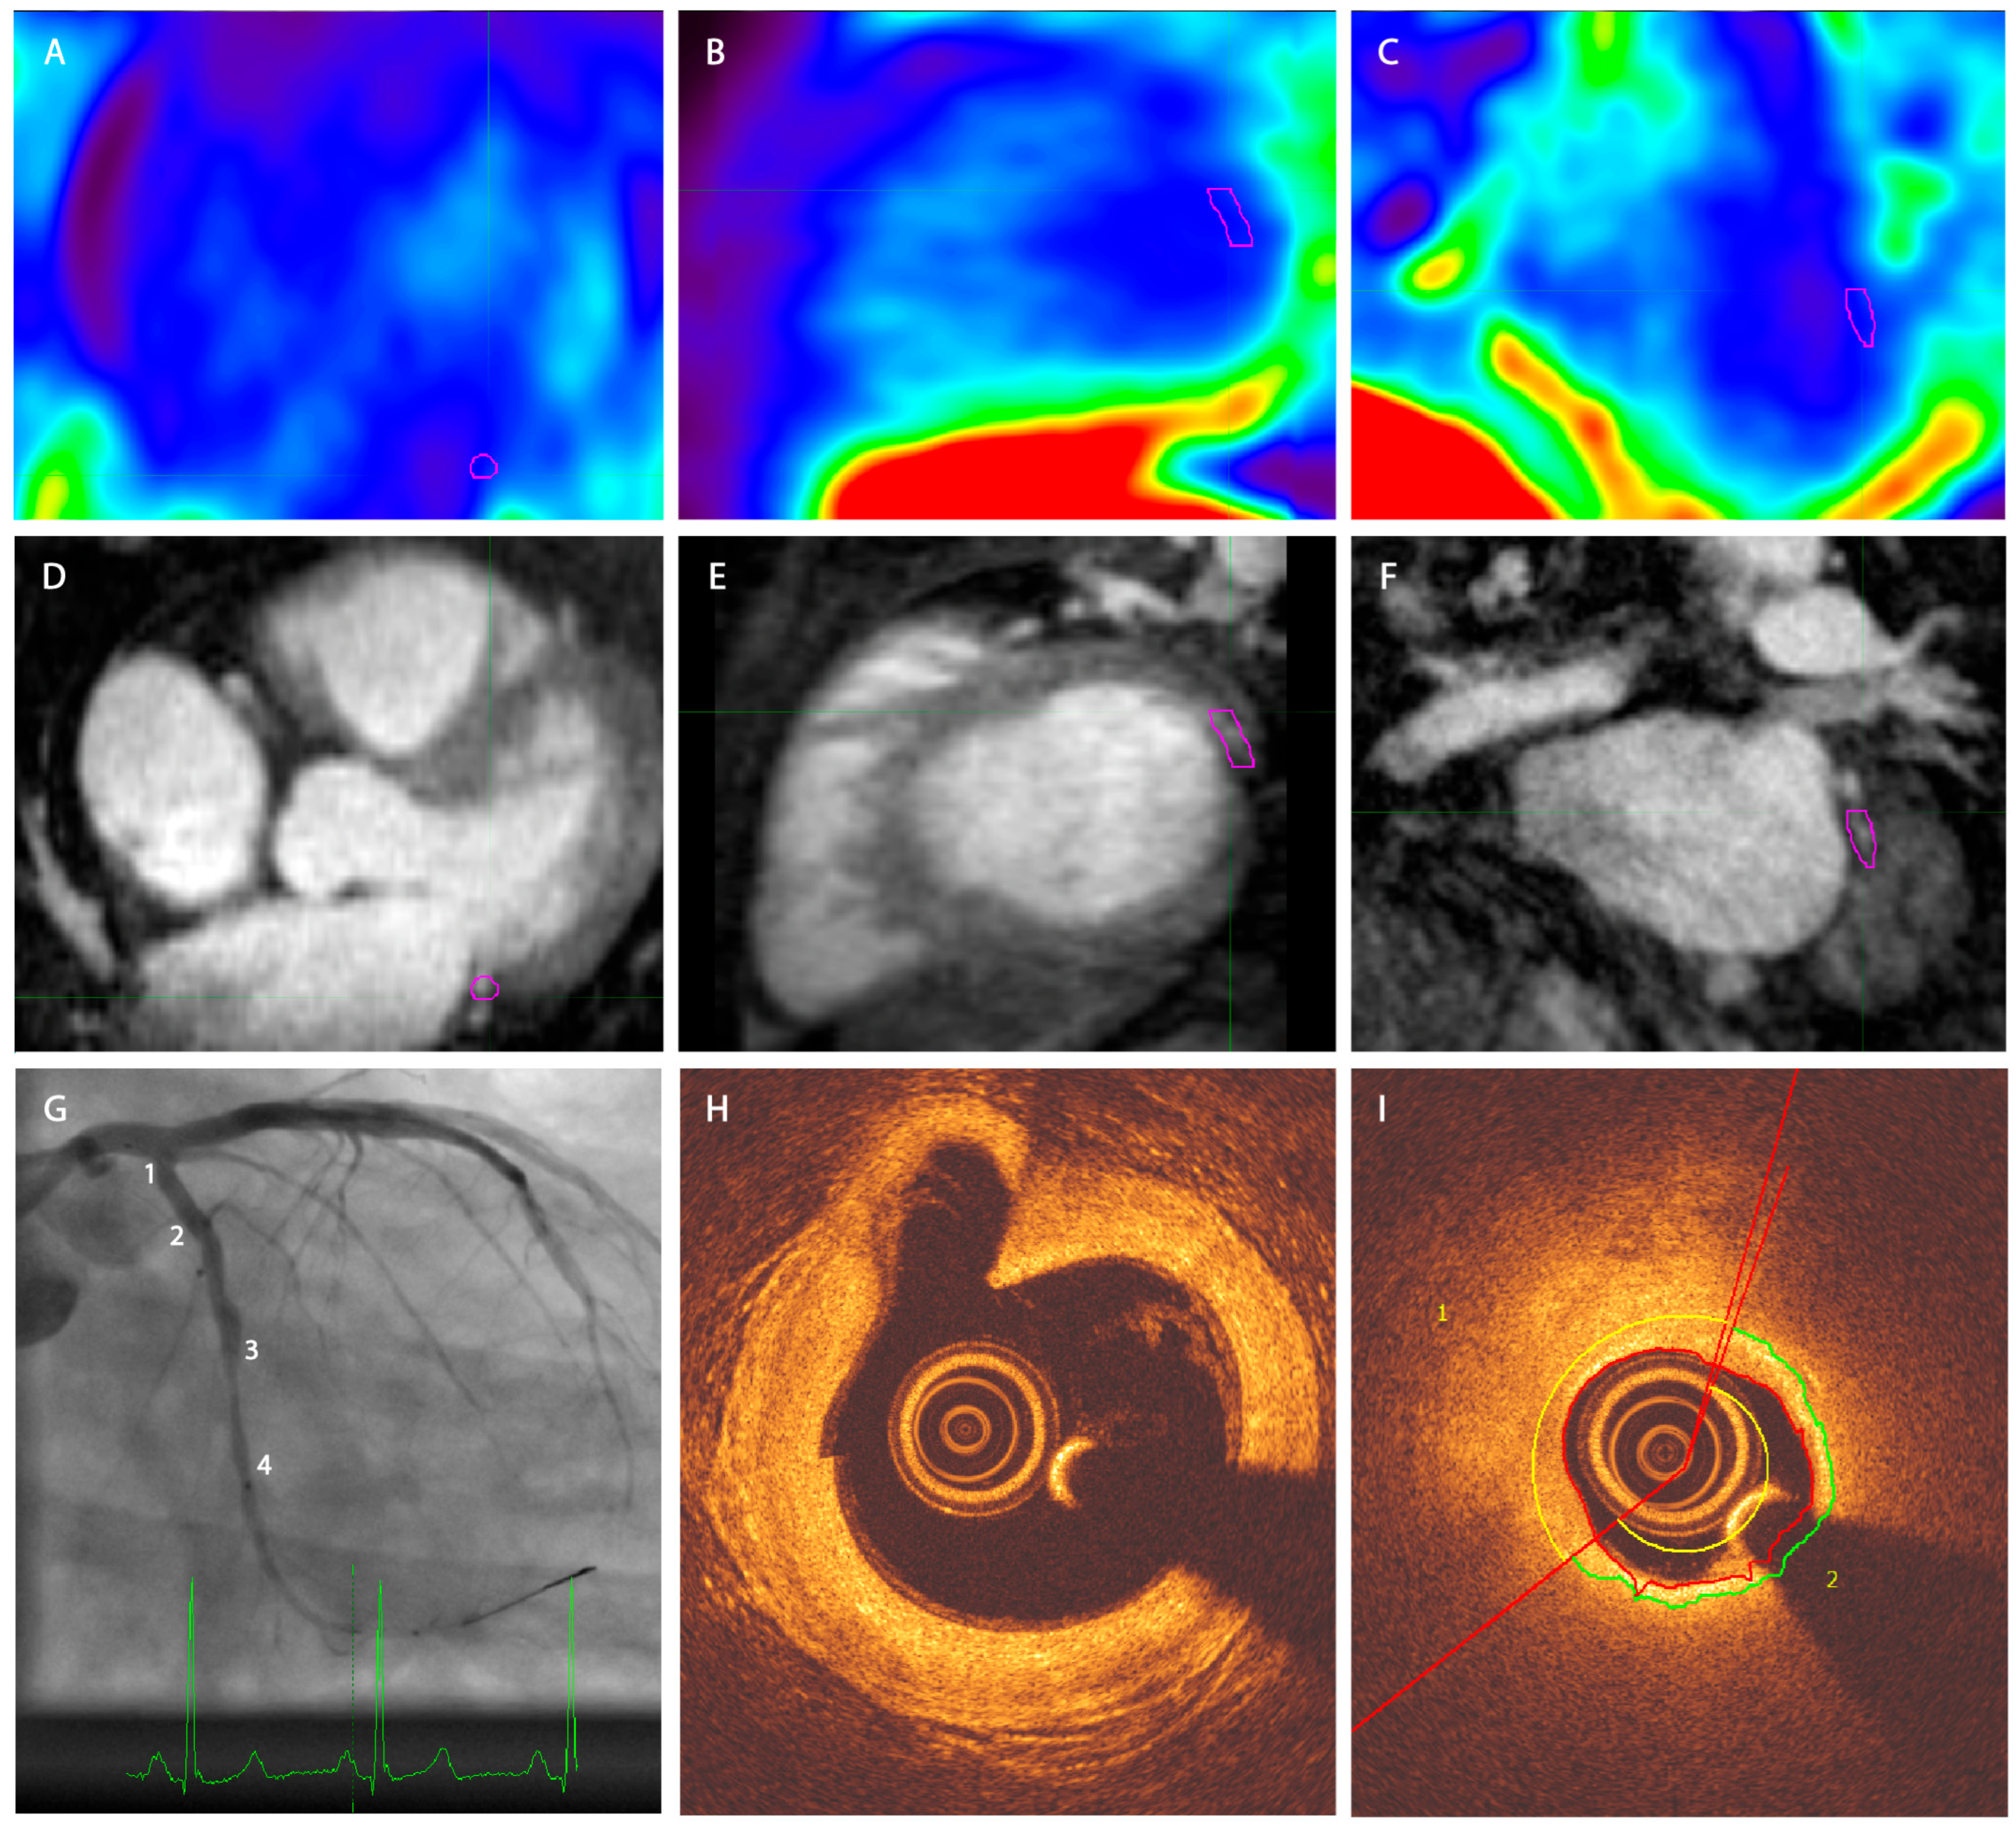

2.2. PET-MR Imaging

2.3. OCT Imaging

2.4. Image Reconstruction

2.5. Image Analysis